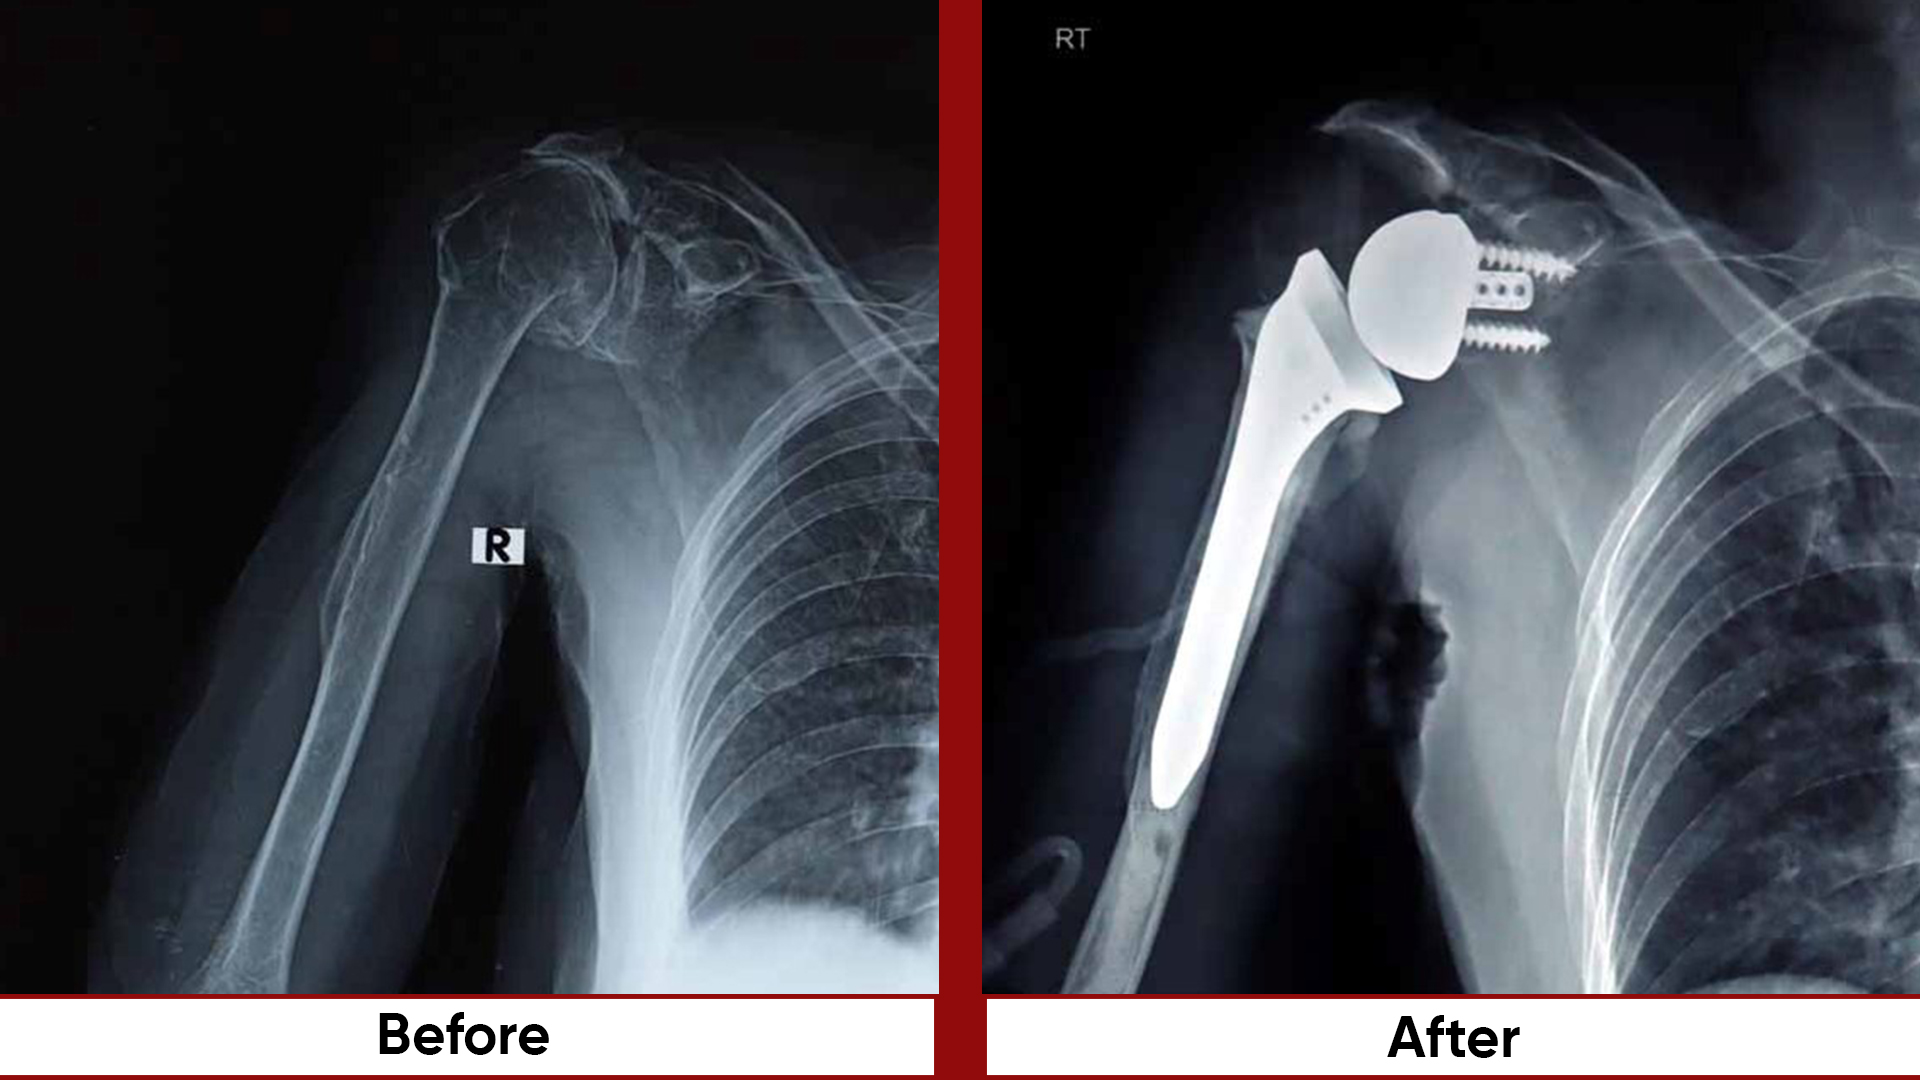

• Arthroplasty